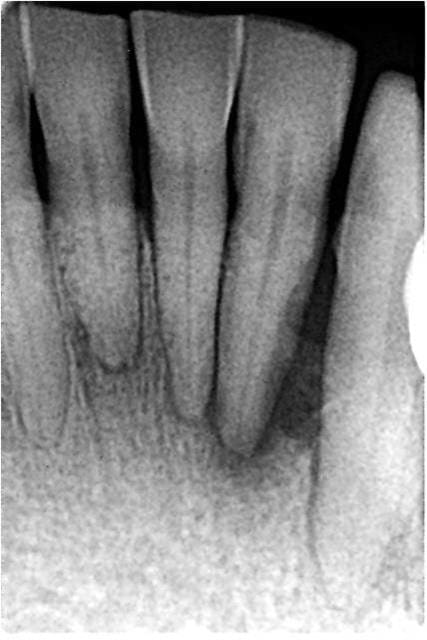

Un exemple de réattache sur une 33, mobile au départ, à 8 mois. Ce cas n'aurait pas pu être traité par un détartrage, et je l'ai fait gratos (implants en cours).

Et 350 euros le traitement, ça me semble plutôt correct, au vu du temps passé, du matériel utilisé et des résultats bénéfiques pour le patient.